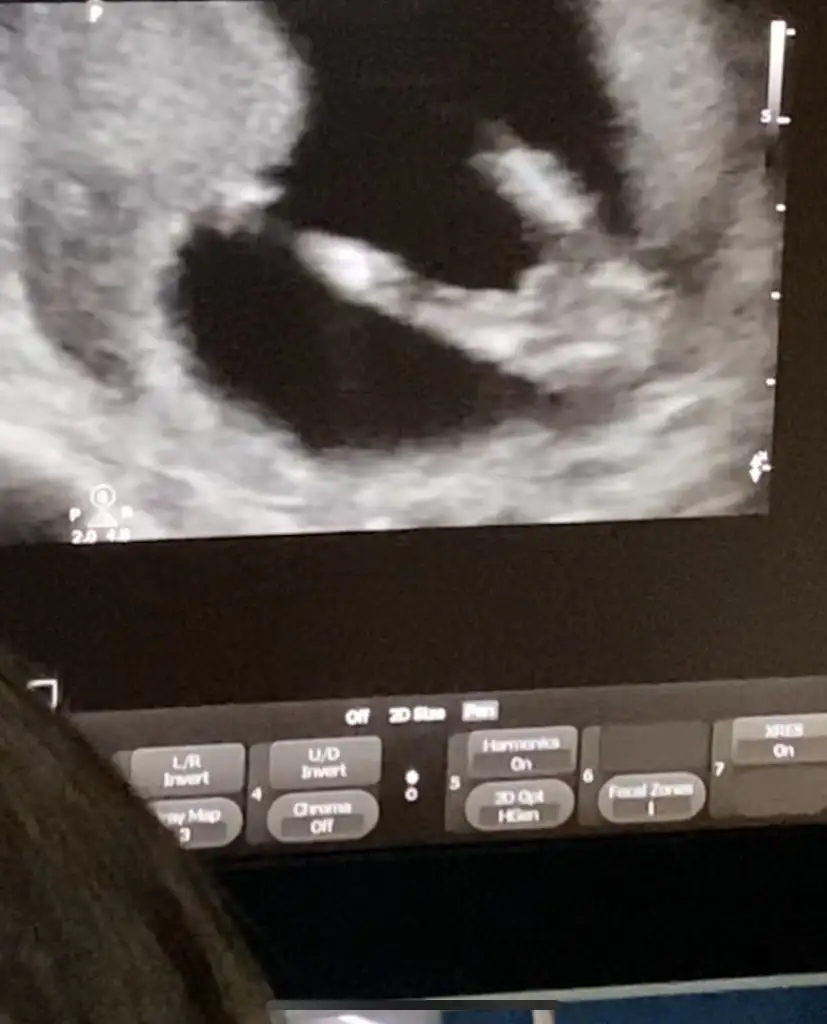

Dr bişey demedi mi kıza bnziyo sankiKızlar banada bakar mısını